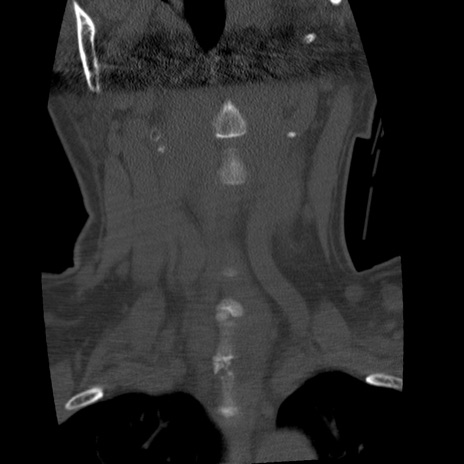

症例50 頚椎CT(冠状断像)

矢状断像